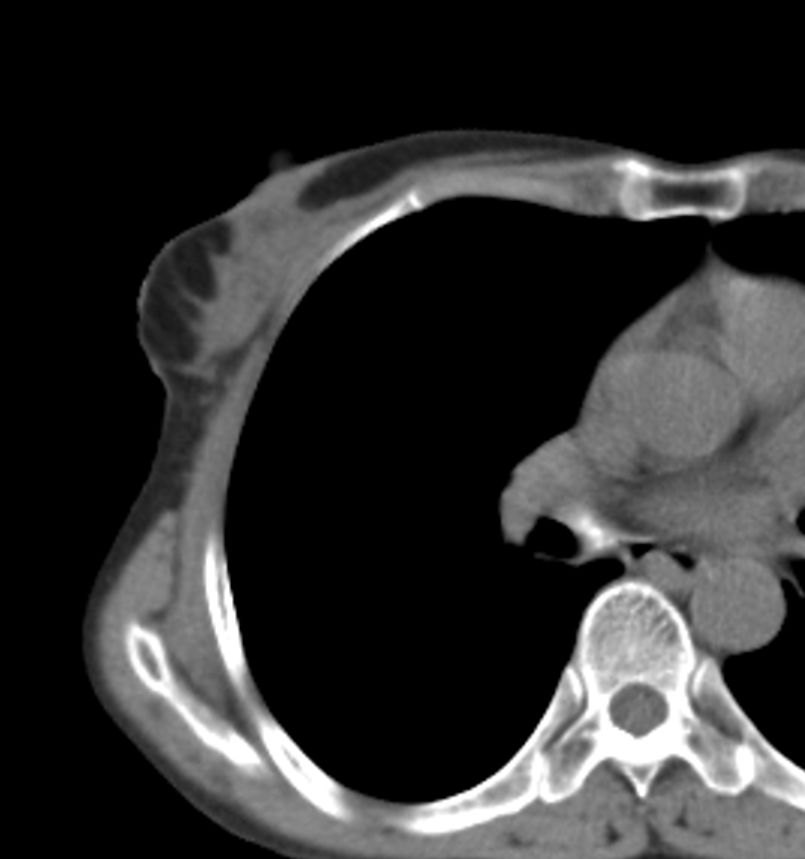

标题: CT21609:右乳包块1年,请各位讨论分析一下,乳腺CA, [打印本页]

标题: CT21609:右乳包块1年,请各位讨论分析一下,乳腺CA,

考虑---右乳癌并胸壁、肋骨、双肺转移。

考虑乳腺癌侵犯肋骨、胸壁及两肺转移可能性大。

右乳癌并胸壁、肋骨、双肺转移。

考虑右侧乳腺癌侵犯肋骨、胸壁及两肺转移。

考虑右侧乳腺癌侵犯肋骨、胸壁及两肺转移可能。

考虑右侧乳癌并胸壁、肋骨及双肺多发性转移。